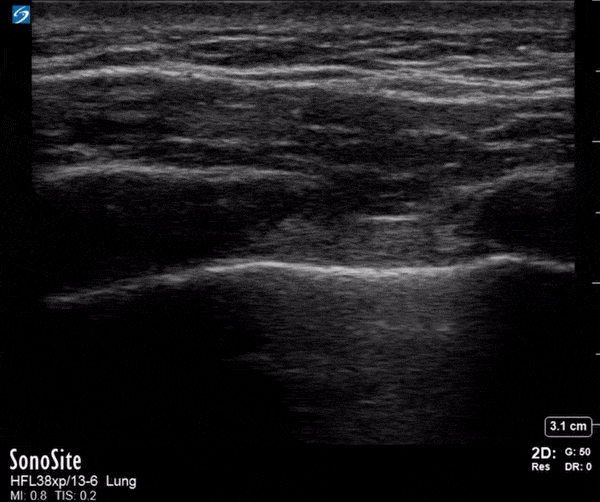

Trauma - Normal Lung Sliding - FAST

11 year old female presented to the emergency department with a puncture wound to her left chest wall. FAST exam did not reveal any intra-abdominal free fluid, and there was lung sliding bilaterally, suggesting no pneumothorax. The patient had her wound explored, repaired, and was discharged home. Contributor: Zach Boivin, MD, @ZachBoivinMD